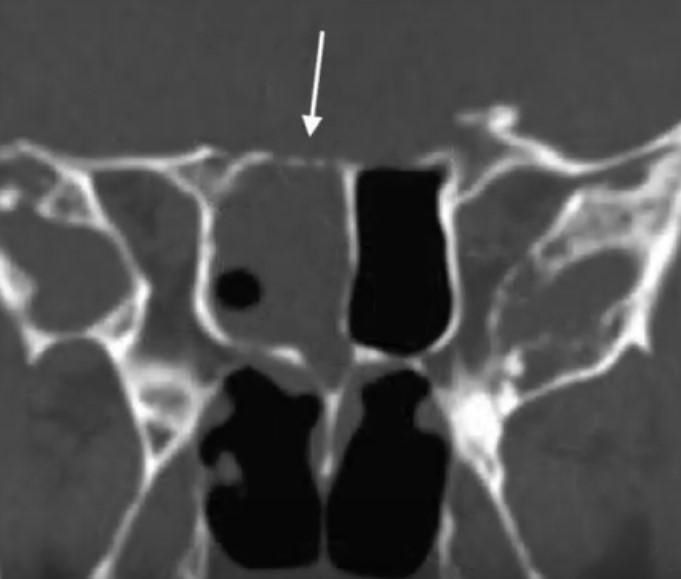

- КТ та МРТ для виявлення місця витоку.

- КТ (комп’ютерна томографія) з контрастом дозволяє виявити анатомічні дефекти та встановити точне місце витоку рідини.

- МРТ (магнітно-резонансна томографія) є додатковим методом для оцінки м’яких тканин та пошкоджень мозкових оболонок.

- КТ-цистернографія використовується для оцінки поширення контрастної речовини через свищевий канал.